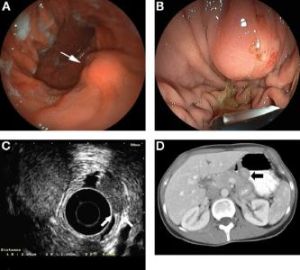

2.內鏡檢查 纖維內鏡,特別是電子內鏡、超聲內鏡均可更清楚看見突入腔內的隆起性病變,或可見潰瘍,甚至異位胰管的開口。雖然內鏡活檢可能獲得病理學診斷,鑒於胰腺異位常埋於黏膜下,甚至更深層,實際上內鏡鉗取較難獲得胰腺異位組織。對位於網膜、腸系膜、肝、脾等消化道外的胰腺異位,腹腔鏡檢查將有所幫助。ERCP 可作為與膽總管結石、乏特壺腹癌、胰頭癌等相鑑別的方法。